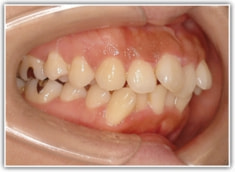

上顎前突ケース

治療法:表の矯正(T21ブラケット)

治療前

治療後(2年後)